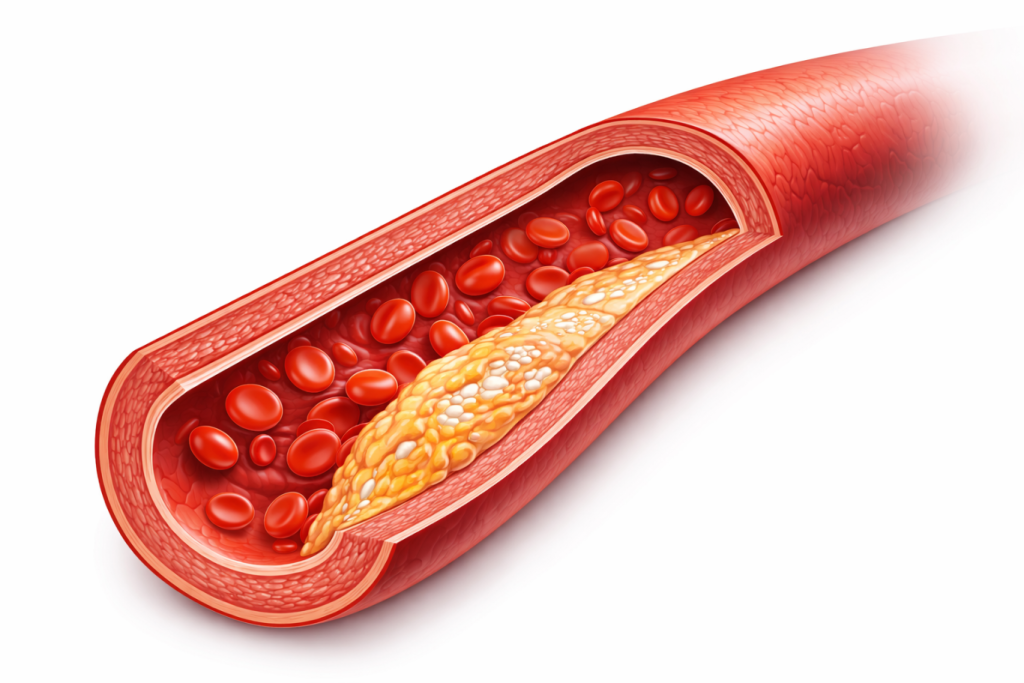

Para una ilustración anatómica conceptual: "Ilustración médica de una sección transversal de una arteria con aterosclerosis, estilo dibujo científico de alta precisión, fondo blanco, iluminación suave, calidad 4k."